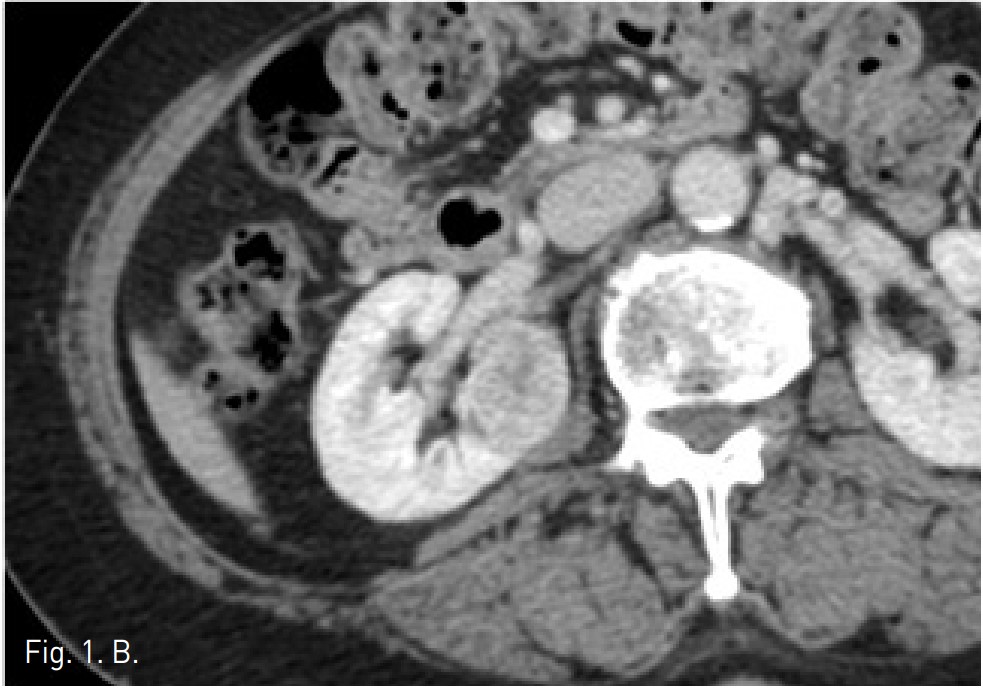

Fig. 1. A

Fig. 1. Kidney MDCT performed for a bulging contoured mass(biopsy proven RCC) in the interpolar portion of right kidney, which showed heterogeneously stong enhancement in the corticomedullary phase and (A) early washout in the nephrographic phase (B).

CT상 우측 신장 cortex 에 약 3.2cm 크기의 돌출하는 양상의 경계가 좋은 고형 종괴가 있음. 종괴는 신우에 인접해 있었으나 신주위 조직이나 신정맥으로의 침습 소견은 보이지 않았음 (Fig. 1A). 환자가 비수술적 치료를 원하여 고주파열치료를 위해 planning US를 시행하였으나 종양의 에코음영이 신실질과 유사하여 뚜렷이 구별되지 않고 (Fig. 2), 신우에 인접하고 있어 합병증의 위험성이 있고, 고주파 열치료만으로는 충분한 치료가 되지 않을 수 있어서, 동맥 색전술과 고주파열치료의 병합 치료를 하였음. 동맥 색전술과 고주파 열치료를 시행하고 9개월 이후 촬영한 CT에서 우측 신종양은 lipiodol이 compact하게 uptake되었으며 주변에 RF ablation zone이 관찰되고 viable portion이 없는 상태임(Fig. 5).